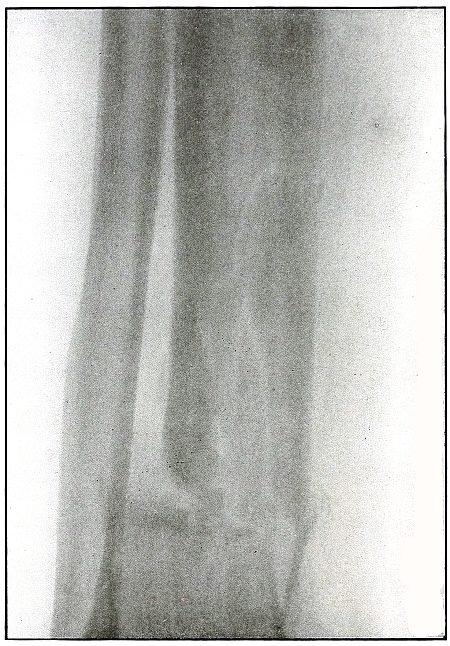

Rifle—Plate 60.

Gunshot Fracture of the Tibia and Fibula,

with Lodgment of the Missile.

The course of the bullet was diagonal from within outward and backward about the middle of the leg, with the impact tangential on the tibia and direct on the fibula. The bullet lies just behind the tibia.

It is apparent that the bullet has been greatly deformed and that its jacket has been badly torn from the core. The force of impact on the object from which it ricocheted must have been contributed by the velocity of short range, which reduced the striking energy so greatly that the bullet was lodged by the resistance of the tibia and fibula.

The wound was not infected, and callus formation shows that repair has begun.

The treatment in such cases, without infection, is noninterference. The lodgment of the missile need not prejudicate the prognosis, and certainly the additional damage in the search for the bullet is not warranted, except under special indications. [Pg 132]